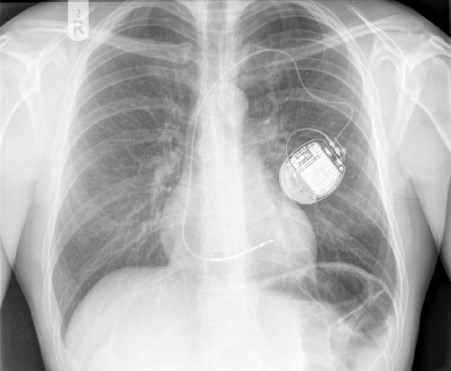

The image is of an x-ray showing an active fixation ICD lead attached to a single chamber ICD. The ICD lead has a single shocking coil.